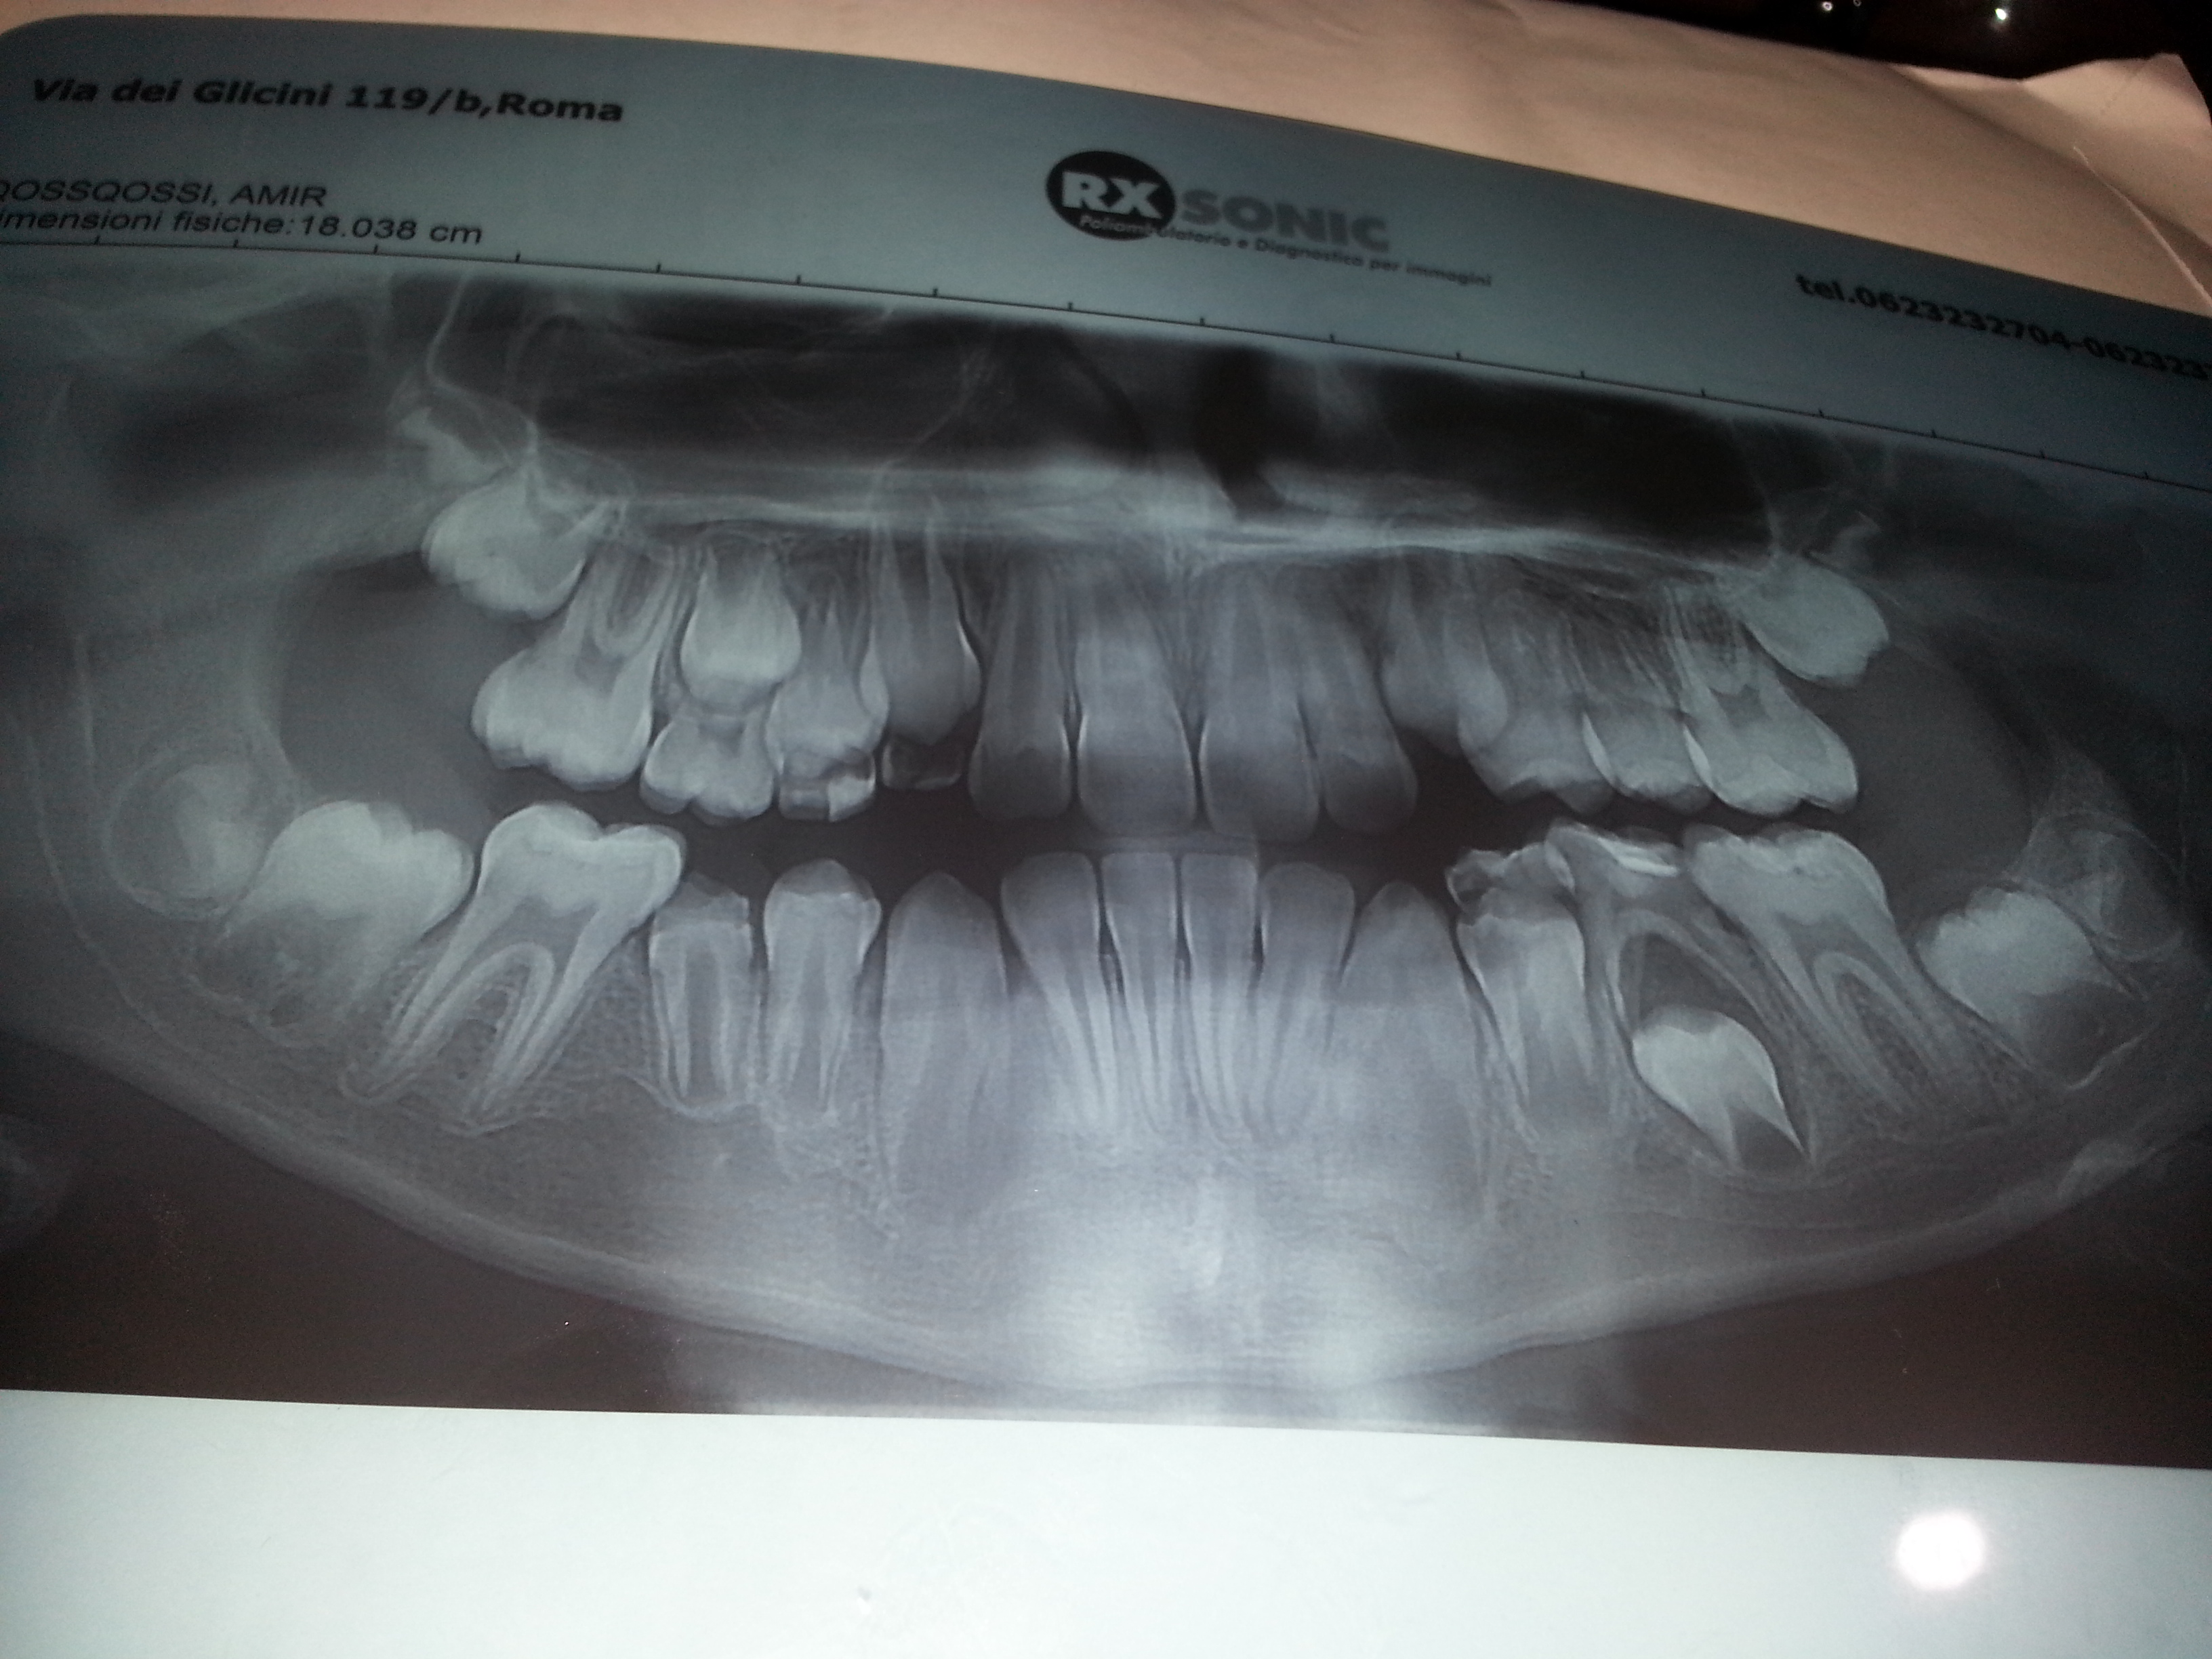

Salve ho un figlio di 9 anni che ha una cisti pericoronale al secondo premolare inferiore sx ancora incluso con persistenza del deciduo sovrastante. Il dentista ha tentato di far spurgare l'ascesso togliendo l'otturazione, ma non è uscito pus. Mi ha detto che va tolto il dente da latte e che la cisti si risolverà da sola. L estrazione sarà difficile. Ci sono rischi x il dente definitivo? Può essere compromesso? Devo fare l estrazione in ospedale e far analizzare la cisti? Saluti

Cara Signora Maria Cristina, buongiorno. Bisogna fare una Diagnosi differenziale tra Cisti Follicolare che però di regola si localizza di lato perché prende origine dal follicolo dentale e una Cisti da Eruzione che invece si localizza sopra la corona del dente in eruzione e sotto il permanente perché origina dai residui dell'epitelio dell'organo dello smalto e si riassorbe dopo l'eruzione del dente. Ancora tra diverse altre Cisti Odontogene e non Odontogene. Soprattutto bisogna fare diagnosi differenziale di tutte le lesioni osteolitiche e non solo cistiche. Parla di "ascesso" infatti. Bisogna fare una Diagnosi Precisa Clinica e non attraverso una OPT postata nel Web. Magari sarebbe servita di più una Rx endorale ma è la visita Clinica, ripeto, l'atto medico-odontoiatrico più autorevole! Non si preoccupi, non pensi neanche all'ospedale o ad altre patologie, non è niente di grave. Le serve solo il Dentista libero Professionista! Attenzione al fatto che il secondo premolare non mi sembra ancora maturo per l'eruzione, quindi se si decidesse di procedere alla avulsione del molarino deciduo, si dovrebbe forse mettere un mantenitore di spazio, dato che l'eruzione di questo permanente avverrebbe tra i 10 e i 12 anni! L'avulsione del deciduo non è affatto "difficile"! Perché è stato detto questo? Stia tranquilla, si rilassi e guardi le cose con meno apprensione, sia pur comprensibile di una mamma per il suo bimbo :) Cari saluti

Gentile Signora, tante parole inutili per un problema talmente semplice e comune a tantissimi bambini della stessa età del suo. Si parla di cisti, vi estrazione, di tante altre cose assurde. Siamo in presenza di una carie penetrante del molaretto deciduo, (se ne vedono tantissime tutti i giorni) che ha creato un ascesso. Basta curare il molaretto e il problema si risolve facilmente senza togliere alcunché. Piu' semplice di così........Cordialmente

Gent sig MARIA CRISTINA il problema e più semplice da quanto da lei descritto..il dente da latte presenta una varie penetrante che ha interessato il tessuto della camera pulsare.. In altre parole l'accesso deriva dalla carie profonda.. La lesione che si vede in radiografia probabilmente si dissolverà con l'eruzione delle dente definitivo.. È necessario seguire il suo bimbo per un po' di tempo... Ma vedrà che le cose si metteranno a posto da sole.. Ci pensa Madre Natura... Ben più lungimirante di alcuni dentisti.. Stia tranquilla, non è grave come lei pensa.. Cordiali saluti..